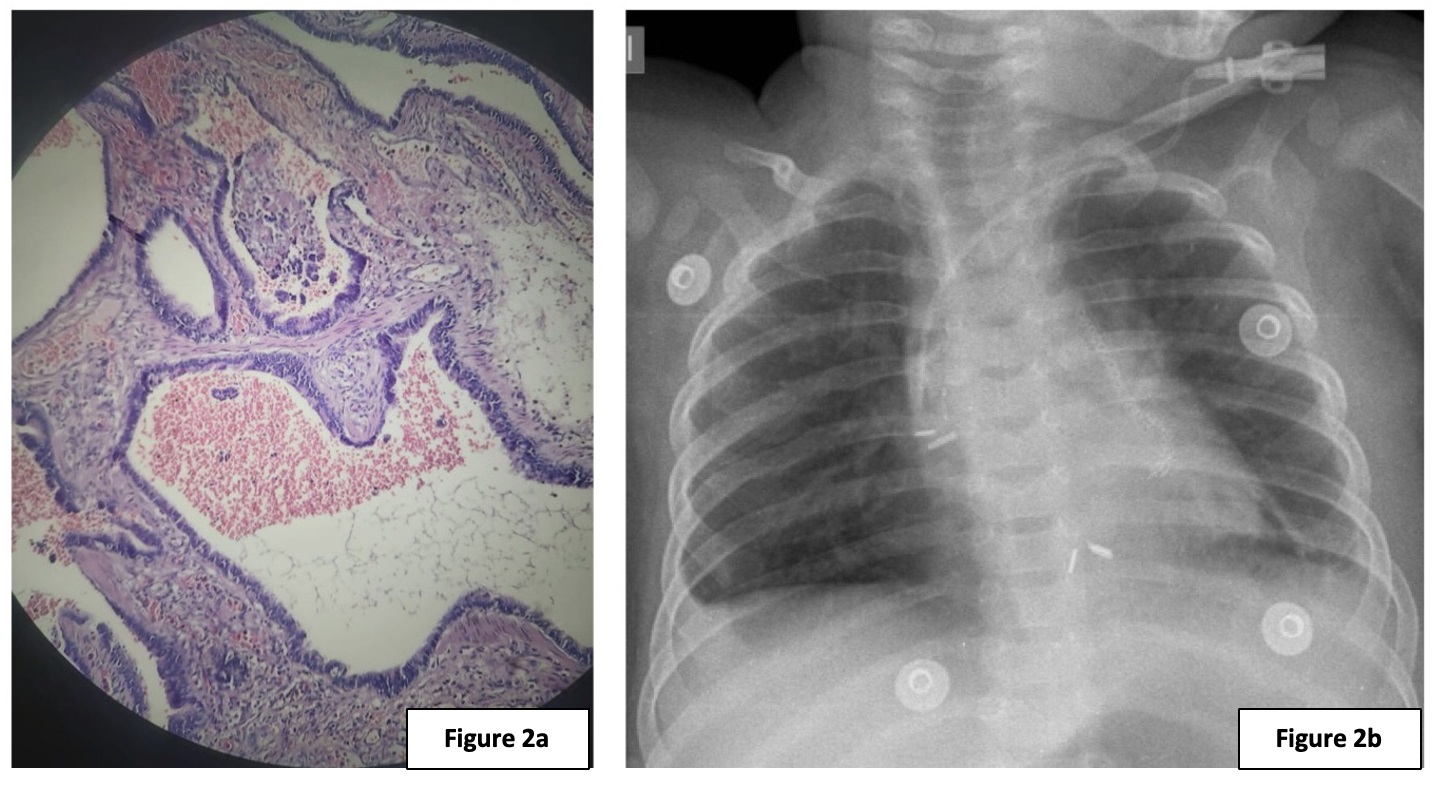

A male neonate born by c-section at 37 weeks (2400g) with a prenatal diagnosis of fetal lung malformation due to bilateral microcystic pulmonary lesions and pelvicalyceal ectasia, presented with a good APGAR score. Imaging studies, including chest x-ray and CT scan with IV contrast (Fig. 1a, 1b) showed bilateral lower lobes multicystic lesions with an isthmus connecting both lower lobes of the lungs. A diagnosis of horseshoe lung with bilateral lower lobe congenital pulmonary airway malformation (CPAM) was made. The patient underwent a right posterolateral thoracotomy with lower right lobectomy, clipping of the inter-pulmonary connection, and chest tube placement on the 14th day of life. Postoperative care was provided in the neonatal intensive care unit (NICU) under mechanical ventilation for 48 hours. The chest tube was removed on the 5th postoperative day; the patient was discharged 9 days later. Histopathology results showed congenital pulmonary airway malformation (Stocker type 2), related to multiple <2 cm cystic lesions with respiratory epithelium.

(a & b): CT scan (axial and coronal section) showing an isthmus connecting the right and left lower lobe with multicystic lesions and surrounding ground glass pattern. The findings depict bilateral lower lobe congenital pulmonary airway malformations with horseshoe lung